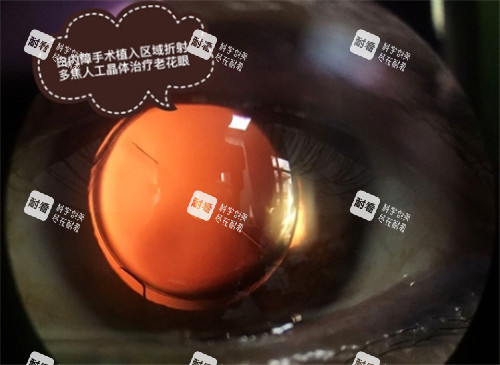

人工晶体类型是造成价格差异的首要因素。单焦点晶体只能提供一个固定距离的清晰视力,价格较亲民,一般在4000-8000元之间。双焦点晶体可满足远、近视力需求,价格区间为12000-25000元。三焦点晶体提供远、中、近全程视力,价格在25000-40000元不等。